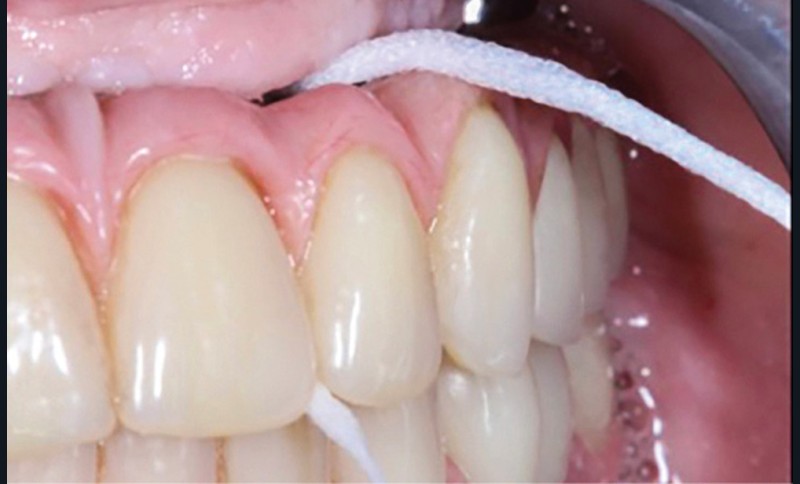

Le projet prothétique pré-implantaire [11] est également l’une des clés du succès ; il doit permettre un positionnement tridimensionnel optimal de l’implant, notamment avec un environnement tissulaire adéquat ; selon la littérature, 2 mm de tissu kératinisé sont nécessaires autour des implants pour fonctionner comme un bouclier autour de lui [12] (fig. 3).